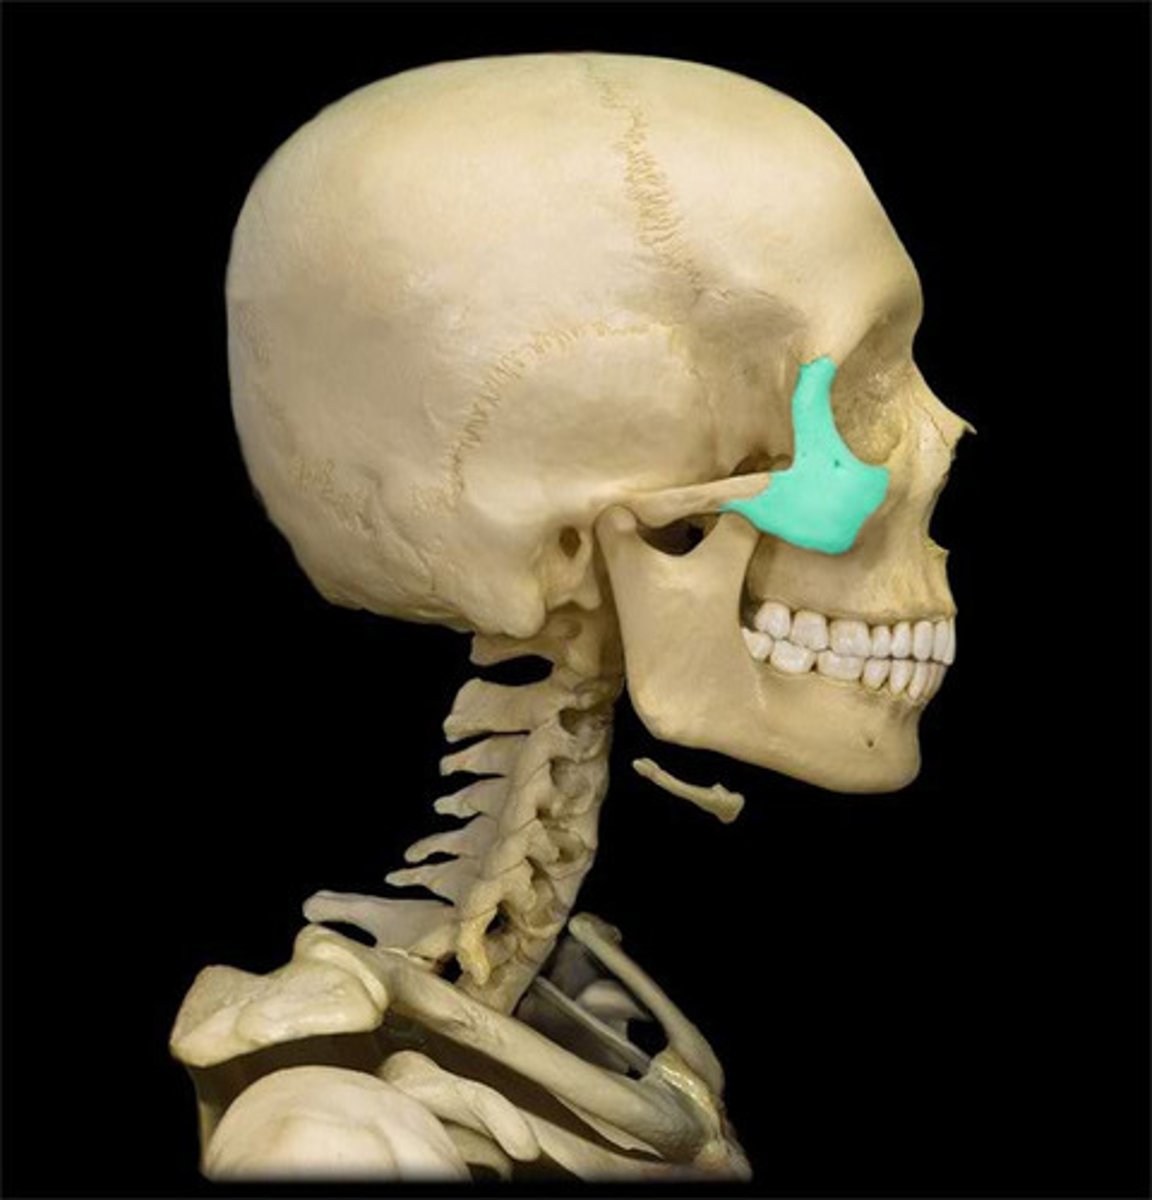

Zygomatic bone

- two zygomatic / malar bones

- temporal process extends posteriorly to join zygomatic process of temporal bone

- maxillary process extends anteriorly to join the maxilla bone

What is this, where is it found and what does it do?